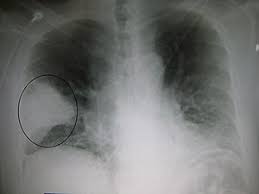

Göğüs Hastalıkları bölümü; akciğer, bronş, soluk borusu, akciğer zarı, boğazı gibi organları içeren solunum sistemimizde oluşan problem ve hastalıklar ile ilgili tanı, tedavi ve hastalık takibini gerçekleştiren tıbbi birimdir.

Astım, kronik öksürük, KOAH, bronşit, zatürre, verem hastalığı, akciğer kanseri gibi birçok hastalık ile ilgilenen Göğüs Hastalıkları; gerekli durumlarda hastalıkların tanı ve tedavisi için multidisipliner bir yaklaşım ile tedavi süreçlerini planlar.

Dikkat edilmediğinde solunum kapasitesini fonksiyonel olarak azaltan göğüs hastalıkları, yaşam kalitesini ve günlük aktiviteleri olumsuz etkileyebilmektedir. Bu nedenle; nefes darlığı, öksürük, hırıltılı solunum, balgam çıkarma ve göğüs ağrısı gibi solunum yolu ile alakalı semptomlar gözlemleniyorsa mutlaka bir göğüs hastalıkları uzmanına başvurulmalı ve bu problem daha ciddi bir duruma dönüşmeden tedavi sürecine başlanmalıdır.